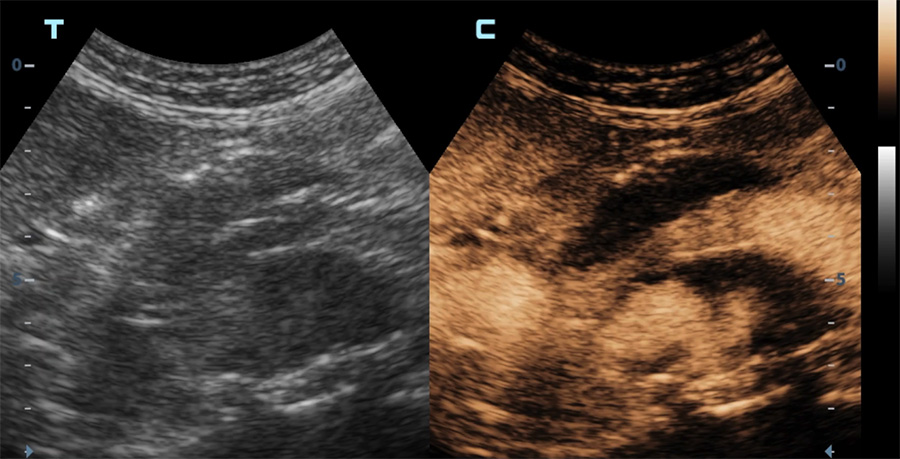

Echographie en mode contraste d’une endoprothèse aortique

Diffusion du produit de contraste dans le sac anévrismal (vue axiale) en dehors de l’endoprothèse (endofuite)

Diffusion du produit de contraste dans le sac anévrismal (vue longitudinale) en dehors de l’endoprothèse (endofuite)